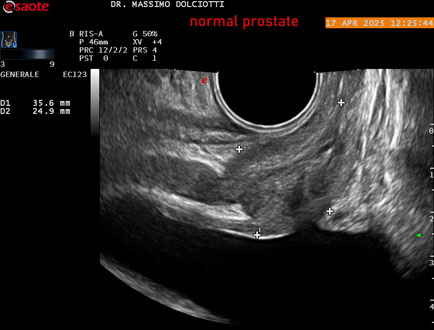

Ecografia del: 17/04/2025

Sonda: Convex Multifrequenza 1-8 MHz, Endocavitaria Multifrequenza 3-9 MHz e 3-13 MHz

Età Paziente: M 35 anni

Motivazione dell'esame: disuria.

Commento all'esame: le immagini ed il video documentano la prostata di ecostruttura regolare e morfovolumetria normale con diametro trasversale di 40 mm, diametro anteroposteriore di 21 mm e diametro longitudinale di 43 mm, con volume prostatico calcolato di 18 cc (v.n. < 20 cc), il profilo prostatico è regolare e netto, non si documentano calcificazioni intraghiandolari, la vascolarizzazione della ghiandola è normale. La vescicola seminale destra presenta diametro longitudinale di 44,4 x 7,8 mm, la vescicale seminale sinistra ha diametro longitudinale di 45,3 mm x 7,2 mm.

Conclusioni: prostata normale (normal prostate).